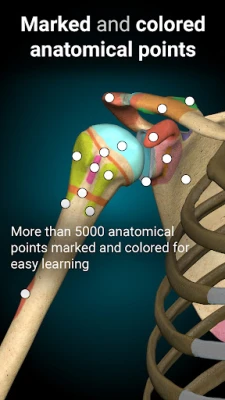

A true and totally 3D app for studying human anatomy, built on an advanced interactive 3D touch interface.

★ You can rotate models to any angles and zoom in and out

★ Remove structures to reveal the anatomical structures below them.

★ 3D location quizzes to test your knowledge

★ Switch on/off different anatomy systems

★ Bones

★ Ligaments

★ Joints

★ Muscles

★ Circulation (arteries, vein and heart)

★ Central nervous system

★ Peripheral nervous system

★ Sense organs

★ Respiratory

★ Digestive

★ Urinary

★ Reproductive ( both male and female)